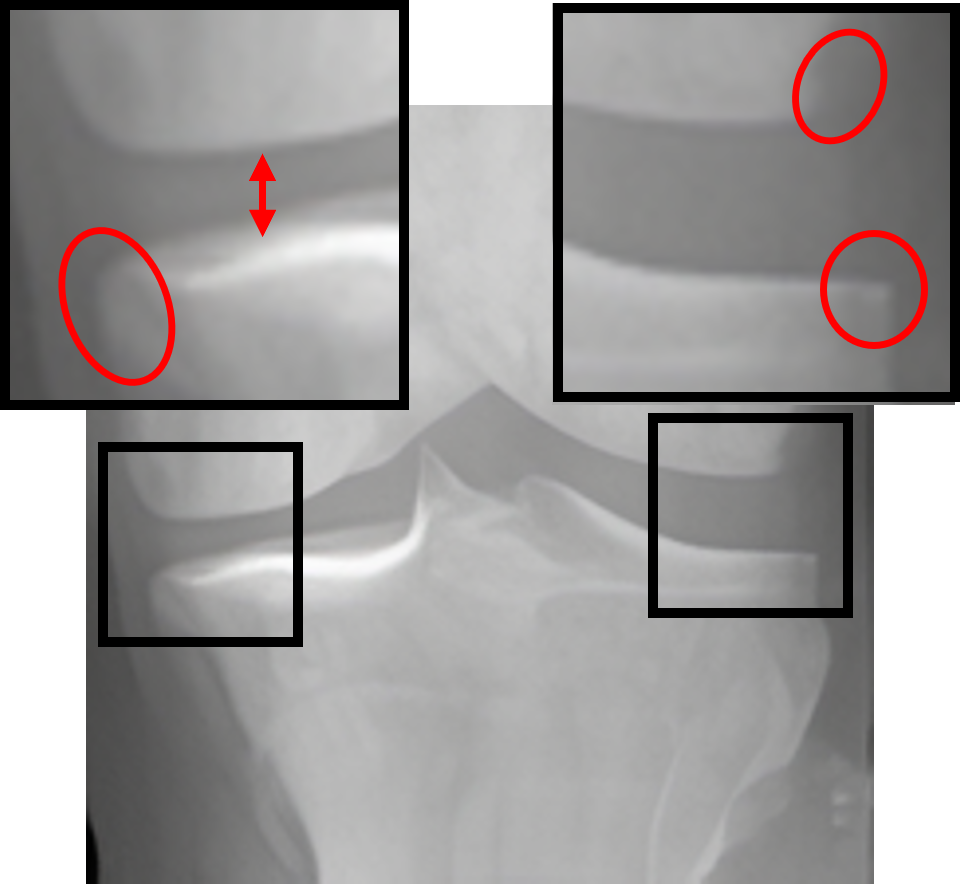

Table 2: Visualization of the synthesized intermediate frames

Input image Synthesized intermediate framessuperscriptSynthesized intermediate frames\stackrel{{\scriptstyle\text{Synthesized intermediate frames}}}{{\makebox[284.52756pt]{\rightarrowfill}}} Input image

xSsubscript𝑥𝑆x_{S} xS(φη=0.25)subscript𝑥𝑆subscript𝜑𝜂0.25x_{S}(\varphi_{\eta=0.25}) xS(φη=0.5)subscript𝑥𝑆subscript𝜑𝜂0.5x_{S}(\varphi_{\eta=0.5}) xS(φη=0.75)subscript𝑥𝑆subscript𝜑𝜂0.75x_{S}(\varphi_{\eta=0.75}) xTsubscript𝑥𝑇x_{T}

KL-0 KL-1∗∗ KL-2∗∗ KL-3∗∗ KL-4

[Uncaptioned image] [Uncaptioned image] [Uncaptioned image] [Uncaptioned image] [Uncaptioned image]

• *

The morphed areas of each frame were highlighted within black boxes, the red arrow and red circle indicate the locations of JSN and osteophyte formation, respectively. A shorter arrow indicates a smaller joint space (i.e., a narrower distance between the tibia and femur), while a larger circle indicates more osteophytes.

• **

The expected labels.

4.2 Visualization of the synthesized intermediate frames

In Table 2, we show the source image xSsubscript𝑥𝑆x_{S}, the target image xTsubscript𝑥𝑇x_{T}, and their intermediate frames (i.e., xS(φη=0.25)subscript𝑥𝑆subscript𝜑𝜂0.25x_{S}(\varphi_{\eta=0.25}), xS(φη=0.5)subscript𝑥𝑆subscript𝜑𝜂0.5x_{S}(\varphi_{\eta=0.5}) and xS(φη=0.75)subscript𝑥𝑆subscript𝜑𝜂0.75x_{S}(\varphi_{\eta=0.75})), which is crucial in understanding how the source images evolve into their registered state. The progressive alignment is quantified by the parameter η𝜂\eta evenly divided into 0.25, 0.5, and 0.75, which represents the extent of transformation at each stage of KOA, corresponding to KL-1, KL-2, and KL-3, respectively. As can be seen, xS(φη=0.25)subscript𝑥𝑆subscript𝜑𝜂0.25x_{S}(\varphi_{\eta=0.25}) shows the initial stage of the morphing process where the morphs are minimal and closely resemble the source image. For xS(φη=0.5)subscript𝑥𝑆subscript𝜑𝜂0.5x_{S}(\varphi_{\eta=0.5}), the morph is more pronounced, introducing clear signs of osteophytes and beginning to show a narrowing of the joint space. It is noteworthy that this frame is critical as it represents the halfway anchor point of the KOA temporal evolution process, showing a balanced mix of characteristics from both the source and target images. xS(φη=0.75)subscript𝑥𝑆subscript𝜑𝜂0.75x_{S}(\varphi_{\eta=0.75}) signifies an advanced stage of morph, introducing moderate multiple osteophytes, definite narrowing of the joint space, some sclerosis, and possible deformity of bone contour.